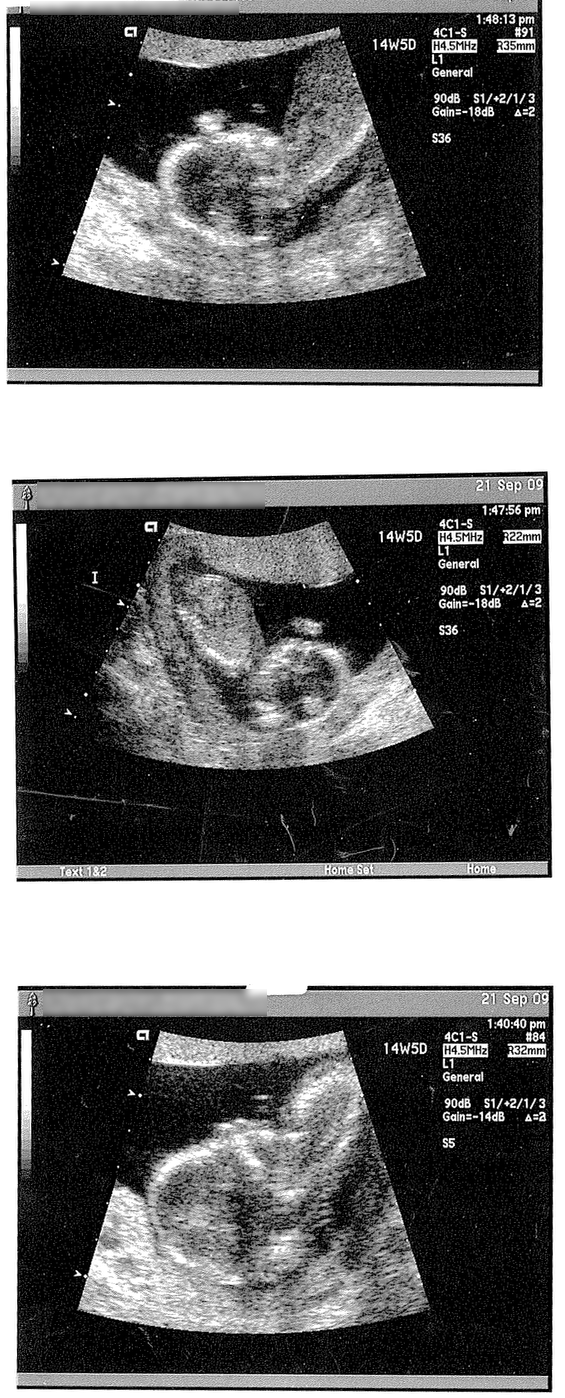

…Only far, far bundle-of-joy-ier. (Click the image for the full size scanination)

We’re due March 17th — that’s right, a St. Patty’s Day baby. They’ll still wear orange, though. *grin*